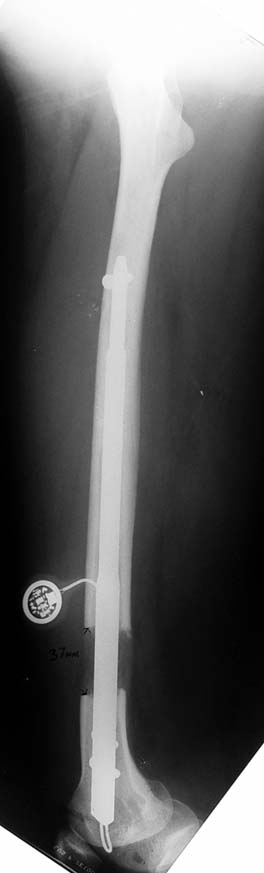

Since 2005 Dr. Mehmet KOCAOGLU is the first most Fitbone operating surgeon in TURKEY. He established the center of excellence for Fitbone surgeries in Istanbul. Fitbone comprises a telescopic nail implant that can extend, powered by an electric motor and controlled by a receiver with an antenna that is buried under the skin; the receiver in turn is controlled by a hand-held radio-frequency transmitter. The procedure for lengthening the lower leg is as follows:

A two-centimetre incision is made at the patient’s knee, and a rimmer is used to create enough space in the bone for a stainless steel nail.

The bone is cut about 14 cm below the knee from the inside with an internal saw. The stainless steel nail is held in place by two screws. The top of the nail is attached to a tiny, plastic-encased receiver that is placed under the skin. The patient controls the lengthening process. By pushing a button on the transmitter when it is placed against the antenna, the built-in motor extends the nail one millimetre per day. When the leg has grown to the desired length, lengthening stops, and the bone is allowed to solidify. The device can be removed about two years after the initial surgery. This procedure, however, comes at a price. While the Ilizarov external fixator costs approximately USD$4,000, and the ISKD implant about USD$8,000, the Fitbone device carries a price tag of roughly USD$15,000 (all prices exclusive of surgery costs).